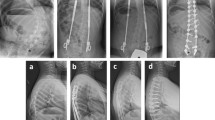

Elasticity was measured at the concave and convex sides of the most curved paraspinal muscles using shear wave elastography at the beginning of treatment, 6 months after treatment, and 12 months after treatment (Fig. 2). Patients were positioned prone with arms placed on the sides of their bodies with their heads in the neutral position and asked to fully relax. Ten regions of interests (ROIs) were marked at the paraspinal muscle lateral to the spinous process at the most curved level after referring to the spine plain film. Four pediatric radiologists under the supervision of one experienced radiologist (M.J.L, 21 years of experience) measured elasticity under the same conditions using the same sonography machine (Aixplorer, SuperSonic Imagine, Aix-en-Provence, France). A high-frequency linear probe (SL10-2) was used to measure elasticity at 1–3 cm depth with an ROI 4 mm in diameter in the paraspinal muscles. The mean elasticity was defined as the mean value of the ten ROIs at each side of the spine.

A representative case of shear wave elastography (SWE) measurement in a 12-year-old girl with adolescent idiopathic scoliosis. (A) The most curved level was determined using the standing whole spine plain film of the anteroposterior view, and it was L1/2. The blue box shows the location of the ultrasound probe when measuring SWE in the paraspinal muscle of the concave side. (B) The SWE image was obtained on the right side (the concave side of this patient) of the paraspinal muscle at the apex of the curve using a high-frequency linear probe. A round region of interest was drawn and the mean value of SWE was obtained (21.1 kPa in this image).